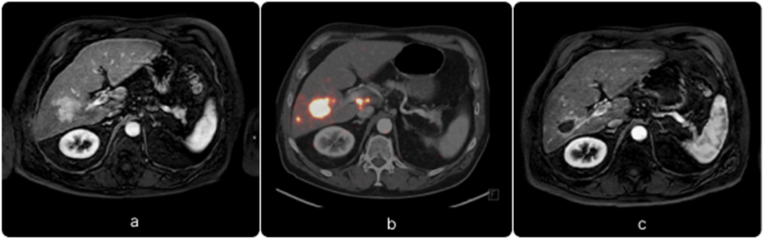

Fig. 2.

Patient with HCC who received radioembolization with 90Y glass microspheres. (a) The baseline image (MRI) demonstrated enhancing hepatocellular carcinoma in segment V/VI. (b) PET/CT image immediately after the treatment, 90Y glass microspheres were selectively injected into the right hepatic artery. As shown, the microspheres are concentrated in the tumor located in segment V/VI. (c) Follow-up MRI 2 months after radioembolization showing complete response to the treatment as the tumor is no longer enhanced.